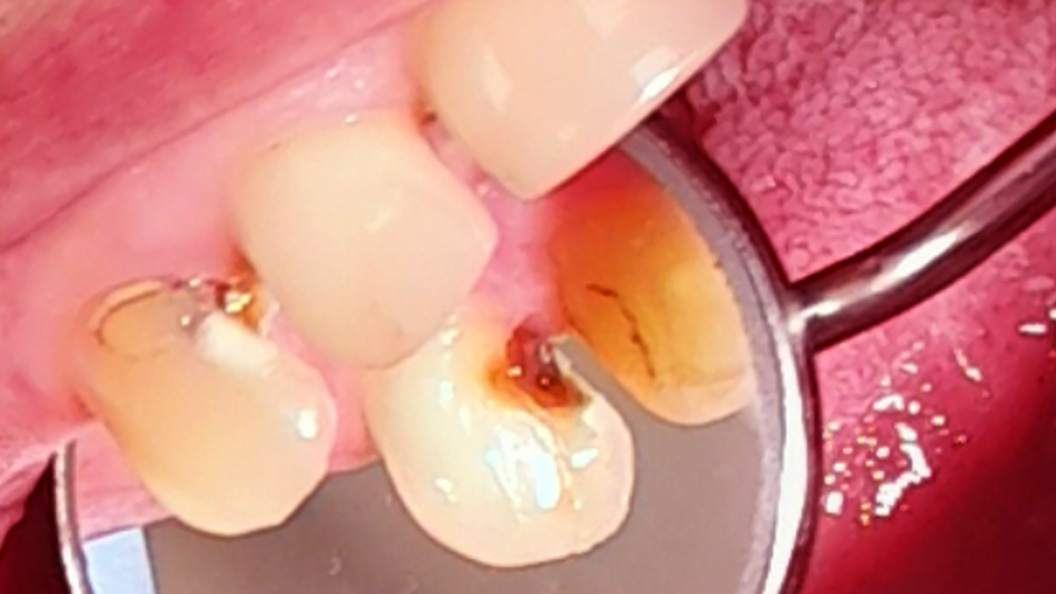

До и после лечения

Пациентка обратилась с жалобами на выпадение пломбы из 13 зуба и длительную боль от температурных раздражителей, ранее были отмечены периодические боли ноющего характера в области 13 зуба. При осмотре врачом-стоматологом-терапевтом Похилько Н. Г. была выявлена глубокая кариозная полость, зондирование которой было резко болезненным в одной точке. Перкуссия была безболезненной. Также при обработке полости под контролем кариес-маркера Похилько Н. Г. выявила сообщение с полостью зуба. Врач поставил диагноз: хронический фиброзный пульпит 13 зуба. Было принято решение о лечении пульпита в 2 посещения с последующей постановкой постоянной композитной пломбы и направлением пациента к ортопеду для покрытия зуба коронкой.